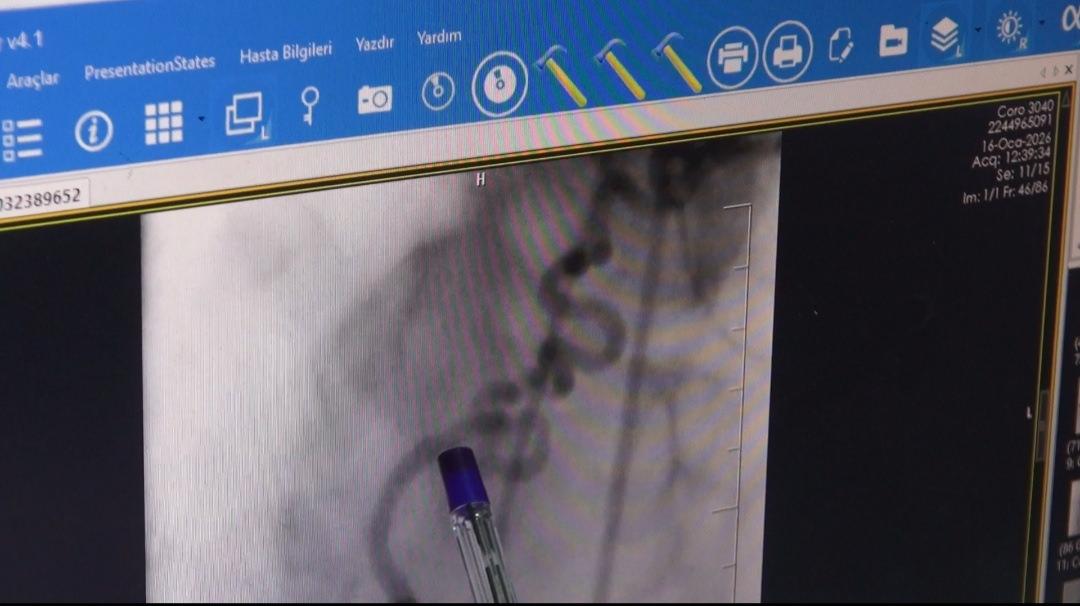

Yapılan anjiyoda kalbin sağ ana arterinden (RCA) köken alan ve akciğere uzanan anormal bir damar tespit edildi. Kardiyoloji Uzmanı Dr. Abdulaziz Taş ile Girişimsel Radyoloji Uzmanı Dr. Abdurrezzak Teken tarafından yapılan değerlendirmede, söz konusu damarın kalbe gitmesi gereken kanın bir kısmını ‘çalarak’ akciğere yönlendirdiği ve bu nedenle hastada göğüs ağrısı ile nefes darlığına yol açtığı belirlendi.

Literatürde nadir görülen koroner çalma (steal) sendromu tanısı konulan hastaya işlem yapılması kararı alındı. Endovasküler yöntemle gerçekleştirilen embolizasyon işlemiyle, kalpten çıkıp akciğere uzanan ve kanı yönlendiren anormal damar başarıyla kapatıldı.